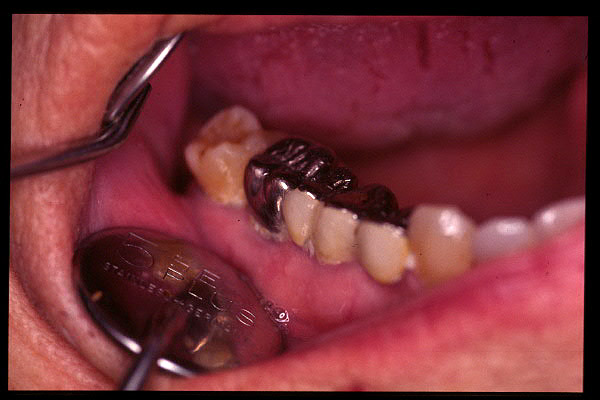

CM Prótesis causante de la anterior hiperplasia